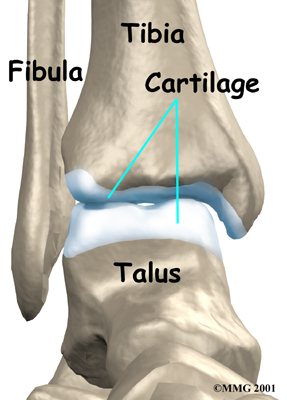

The ankle joint is made up of three bones: the lower end of the tibia (shinbone), the fibula (the small bone of the lower leg), and the talus (the bone that fits into the socket formed by the tibia and fibula).

The talus sits on top of the calcaneus (the heelbone). The talus moves mainly in one direction. It works like a hinge to allow your foot to move up and down.

Inside the joint, the bones are covered with a slick, smooth material called articular cartilage. Articular cartilage is the material that allows the bones to move against one another in the joints of the body. The cartilage lining is about one-quarter of an inch thick in most joints that carry body weight, such as the ankle, hip, or knee. It is soft enough to allow for shock absorption but tough enough to last a lifetime, as long as it is not injured.